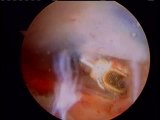

Dr. Gil Lederman talks about knee resurfacing. Gil Lederman is an experienced medical doctor and a certified oncologist with 25 years of experience.